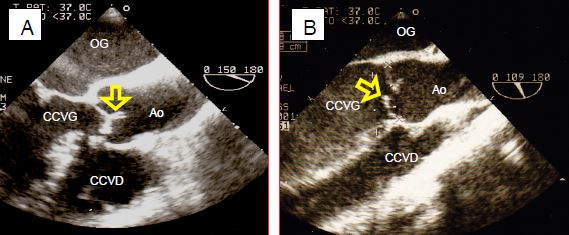

Figure 11.136 : Insuffisance aortique. A : jet d’IA central en cas de dilatation de l’anneau (maladie de la racine de l’aorte). B : jet excentrique an cas de lésion d’une cuspide aortique (prolapsus). C : mesure du diamètre de la vena contracta juste en aval de la valve. D : rapport du diamètre du jet à celui de la chambre de chasse au même niveau.